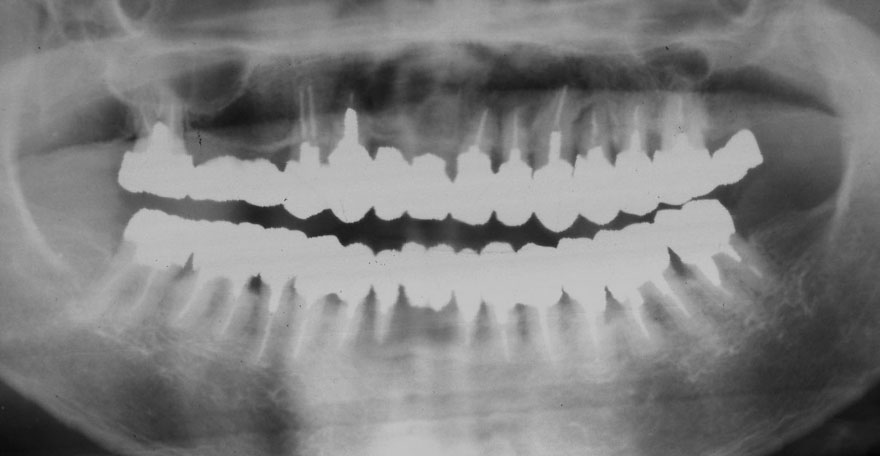

初診時 51歳 男性 平均歯槽骨喪失量:2.83mm

21年後 72歳

平均歯槽骨喪失量:2.51mm

21年間再生量:+0.32mm

年間再生速度:+0.015mm

(ケア頻度:1.20ヵ月ごと)